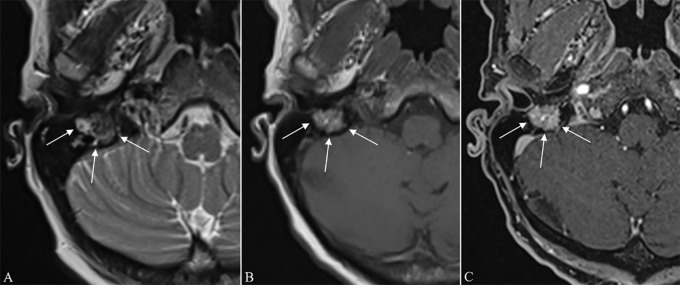

We report the case of a 54‑year‑old woman with 3‑year‑history of right facial paralysis. Computed tomography (CT) and magnetic resonance imaging (MRI) findings were highly suggestive of a primary paraganglioma (PGL) of the facial nerve canal (FNC). 68Ga‑DOTATATE positron emission tomography (PET)/CT confirmed the neuroendocrine nature of the tumor. Teaching point: The combined imaging findings of permeative bone destruction, rapid wash‑in and wash‑out perfusion, and 68Ga‑DOTATATE tracer uptake in a lesion arising from the mastoid segment of the FNC are diagnostic of a primary PGL of the FNC and may obviate the need for histological confirmation.

我们报告一例54岁女性,有3年的右侧面瘫病史。计算机断层扫描(CT)和磁共振成像(MRI)的结果高度提示面神经管(FNC)原发性副神经节瘤(PGL)。68Ga - DOTATATE正电子发射断层扫描(PET)/CT证实了肿瘤的神经内分泌性质。教学要点:FNC乳突段病变的穿透性骨破坏、快速洗入和洗出灌注以及68Ga - DOTATATE示踪剂摄取的综合影像学表现可诊断FNC原发性PGL,可能无需组织学证实。